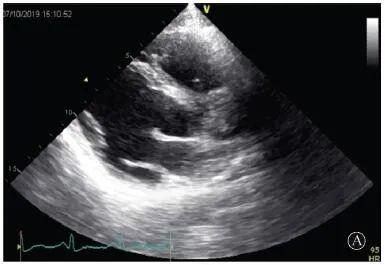

患者入院后無(wú)特殊不適,心率70次/min,血壓110/60 mmHg,心功能Ⅱ級(jí)。查血常規(guī):血紅蛋白139 g/L,白細(xì)胞7.39×109/L,血小板221×109/L。尿常規(guī)、便常規(guī)+潛血均正常。生化:丙氨酸氨基轉(zhuǎn)移酶38 U/L,白蛋白47 g/L,鉀3.9 mmol/L,肌酐(酶法)65 μmol/L,總膽固醇3.52 mmol/L,低密度脂蛋白膽固醇2.08 mmol/L。CK:1256→487 U/L,CK-MB 9.7→3.8 μg/L,cTnI 85.90→68.50 pg/ml。N末端B型利鈉肽原70 pg/ml。CK同工酶電泳:肌酸激酶MM質(zhì)量100.0%(此時(shí)CK-MB已正常)。血沉1 mm/第1小時(shí),高敏C反應(yīng)蛋白1.61 mg/L;補(bǔ)體:C3 0.876 g/L,C4 0.174 g/L。免疫球蛋白:IgG 9.52 g/L,IgA 1.73 g/L,IgM 0.62 g/L。血清蛋白電泳未見(jiàn)M蛋白。糖化血紅蛋白5.1%。乳酸(運(yùn)動(dòng)前)1.1 mmol/L,乳酸(運(yùn)動(dòng)中)6.6 mmol/L,乳酸(運(yùn)動(dòng)后)7.8 mmol/L。肌炎抗體譜:抗PM-SCL75(+),余均(-)。心電圖:aVL、V5、V6導(dǎo)聯(lián)T波倒置(圖2)。冠狀動(dòng)脈CT未見(jiàn)明顯異常。超聲心動(dòng)圖:左室舒張末內(nèi)徑55 mm,左室收縮功能減低,心尖部、左室壁普遍運(yùn)動(dòng)減低,以左室下后壁為著,左室下后壁肌小梁明顯增多可見(jiàn)隱窩,疏松層與致密層之比為1.7;左室射血分?jǐn)?shù)(雙平面)45%;右冠狀動(dòng)脈開(kāi)口6.5 mm,開(kāi)口處未見(jiàn)明確瘤樣擴(kuò)張(圖3)。

A:胸骨旁長(zhǎng)軸平面,左室舒張末內(nèi)徑略增大,室壁無(wú)明顯增厚;

協(xié)和疑難︱第67例:臨床表現(xiàn)胸痛伴肌酸激酶升高

B:胸骨旁左室短軸切面心尖水平,可見(jiàn)心肌肌小梁增多,其內(nèi)可見(jiàn)隱窩(箭頭所示)

圖3 患者入院后超聲心動(dòng)圖